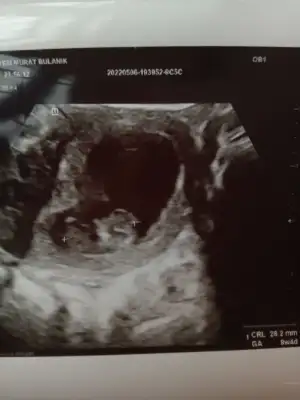

Merhaba bende çok merak ettim :) karından ultrason 9+4 gün

• IMG_20220506_143459.webp

IMG_20220506_143459.webp

18,9 KB · Görüntüleme: 50